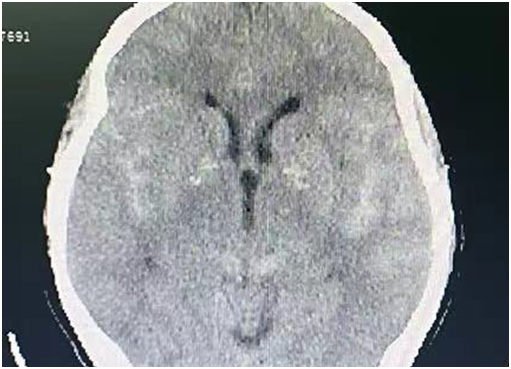

春節(jié)期間,70歲的陳奶奶因頭痛、嘔吐1天后,前往惠州三院急診就診。接診醫(yī)師迅速判斷:患者可能患腦出血。檢查后,從頭顱CT可見,陳奶奶蛛網膜下腔出血。醫(yī)生結合出血部位及形態(tài)考慮,陳奶奶顱內動脈瘤破裂的可能性很大。